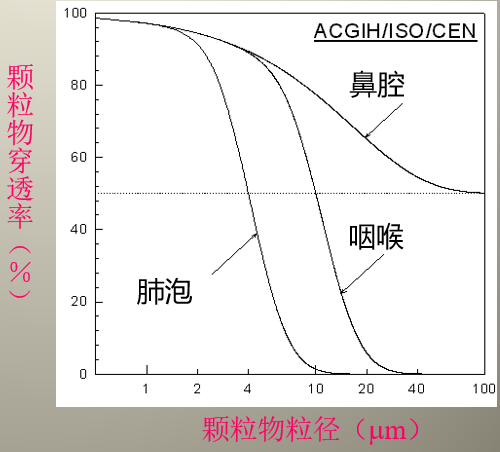

空气中的有害物质无处不在,大到肉眼可见,小到几微米的颗粒物无时无刻不在挑战着我们自身肺部保护的能力。20微米直接进入肺,5微米入肺泡。

从图片我们不难看出,一旦颗粒物在1微米以下,其穿透鼻腔、咽喉、肺泡的穿透率是100%。如果颗粒物在5微米以下,有80%的概率顺利通过鼻腔、咽喉,进入肺部,而我们的肺就变成了一个小型不可逆过滤器。5微米是什么概念?我来举个例子,普通人的头发丝直径是30微米。那我们怎么保护自己的肺呢?如果您的工作环境恶劣,那么佩戴自吸过滤式防颗粒物KN100呼吸器是必不可少的。它的过滤效率能达到99.99%,呼气阻力是35 Pa,而总重量只有140g。不会憋闷、不会沉重!